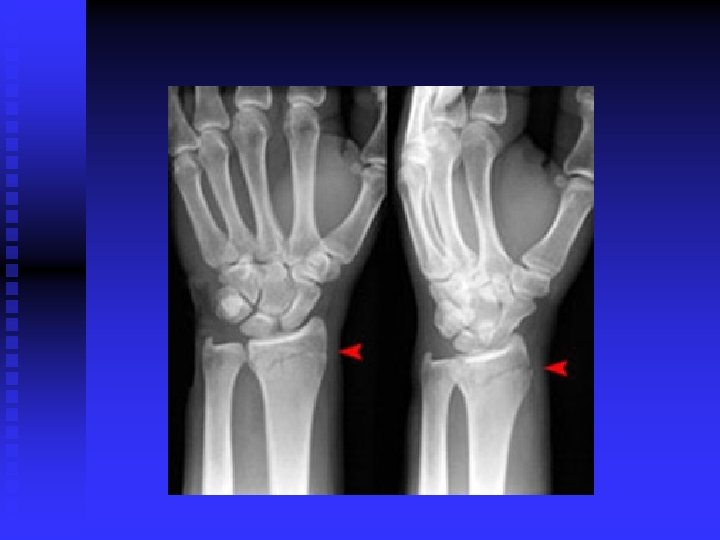

Carpal Tunnel Syndrome n n Median nerve compression within the carpal tunnel is the most common peripheral nerve entrapment syndrome. Any condition that decreases the cross sectional area of the carpal tunnel or increases the volume of its contents may cause the pathology. EX: lunate dislocation; distal radius fracture, sustained flexion or extension postures, fluid retention, synovitis